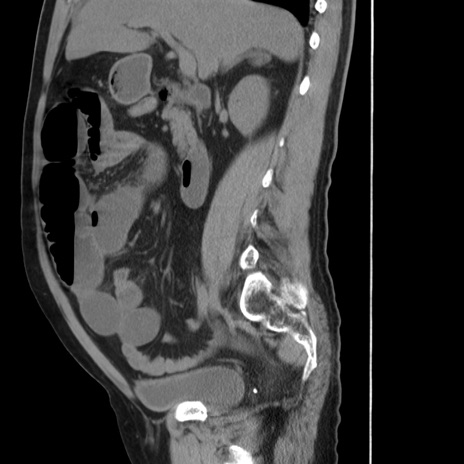

症例20(矢状断像)

【症例】 60歳代男性

【主訴】 腹部膨満、嘔吐

【現病歴】5日前頃より倦怠感を認め食事量減少し4日前の朝嘔吐、食事摂取困難となった。 3日前近医受診し点滴施行され整腸剤などを処方された。 当日他院を受診し、腹部膨満著明、炎症反応の上昇(CRP10.8、WBC11200)あり、紹介受診となる。

【身体所見】 意識JCS1 受け答えがはっきりしないBP 111/57mHg、 P 67bpm、、BT35.2°C、SpO2 97%(RA)、 腹部:膨隆、打診で鼓音あり、全体的に圧痛有り、腸蠕動音(-)、反跳痛ははっきりせず。

【データ】WBC 11400、CRP 14.20